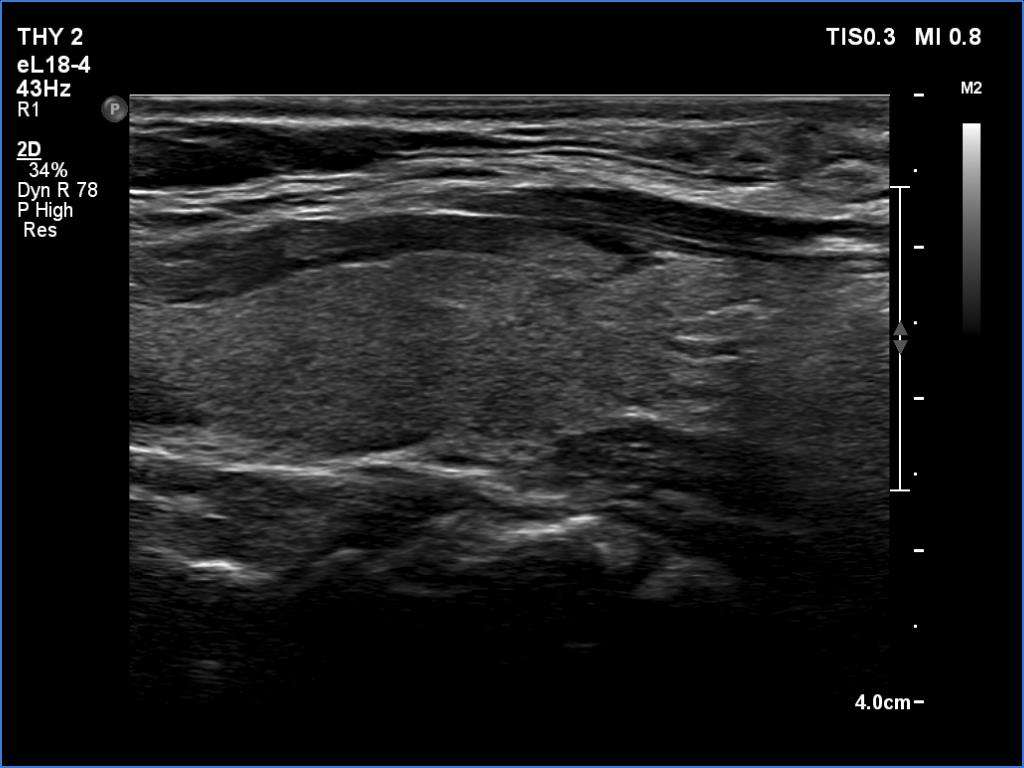

The operated thyroid - case 1641

Four weeks after the surgery (ultrasonographic picture 6)

Left lobe, longitudinal scan.